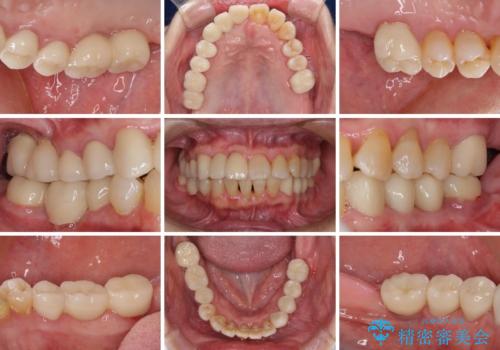

数多くの外科処置を行ったため、治療期間は長期間となりました。

一方、外科処置をしっかりと行ったことで、歯周病の状態は改善され、安定した状態にしあげることができました。